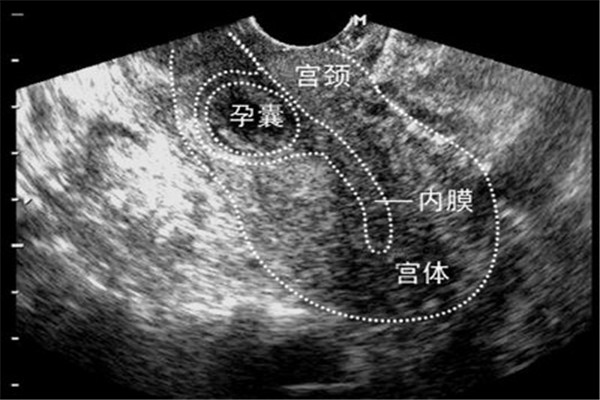

子宫内膜的品质:子宫内膜是胚胎着床的地方,子宫内膜如果厚度适当,血流丰富且细胞分裂良好,相当于肥沃疏松的土壤,会增加胚胎着床率,反之,若子宫内膜太薄,血流量不够,荷尔蒙分泌缺乏,这种内膜就相当于盐碱地,胚胎就不易着床。另外在植入胚胎的时候,子宫会有收缩的动作,有时候胚胎甚至会被推到输卵管,造成子宫外孕,所以胚胎植入后要有充分的卧床休息,补充足够的黄体素,以增加着床率减少外孕的比率